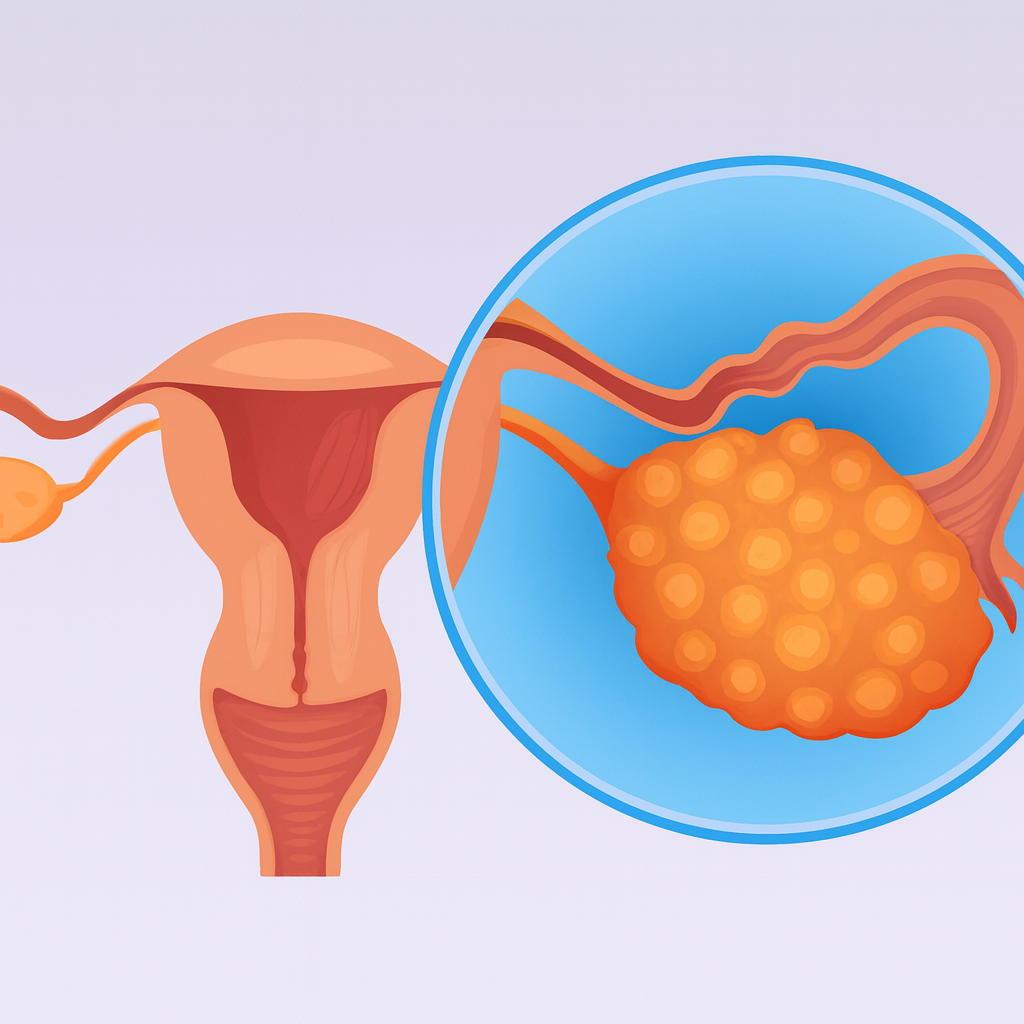

A Síndrome dos Ovários Policísticos (SOP) é uma condição endócrina que afeta mulheres durante os anos reprodutivos. Ela se caracteriza por irregularidades na ovulação, excesso

A Síndrome dos Ovários Policísticos (SOP) é uma condição hormonal que impacta cerca de 10% das mulheres em idade fértil. Ela é marcada por ciclos